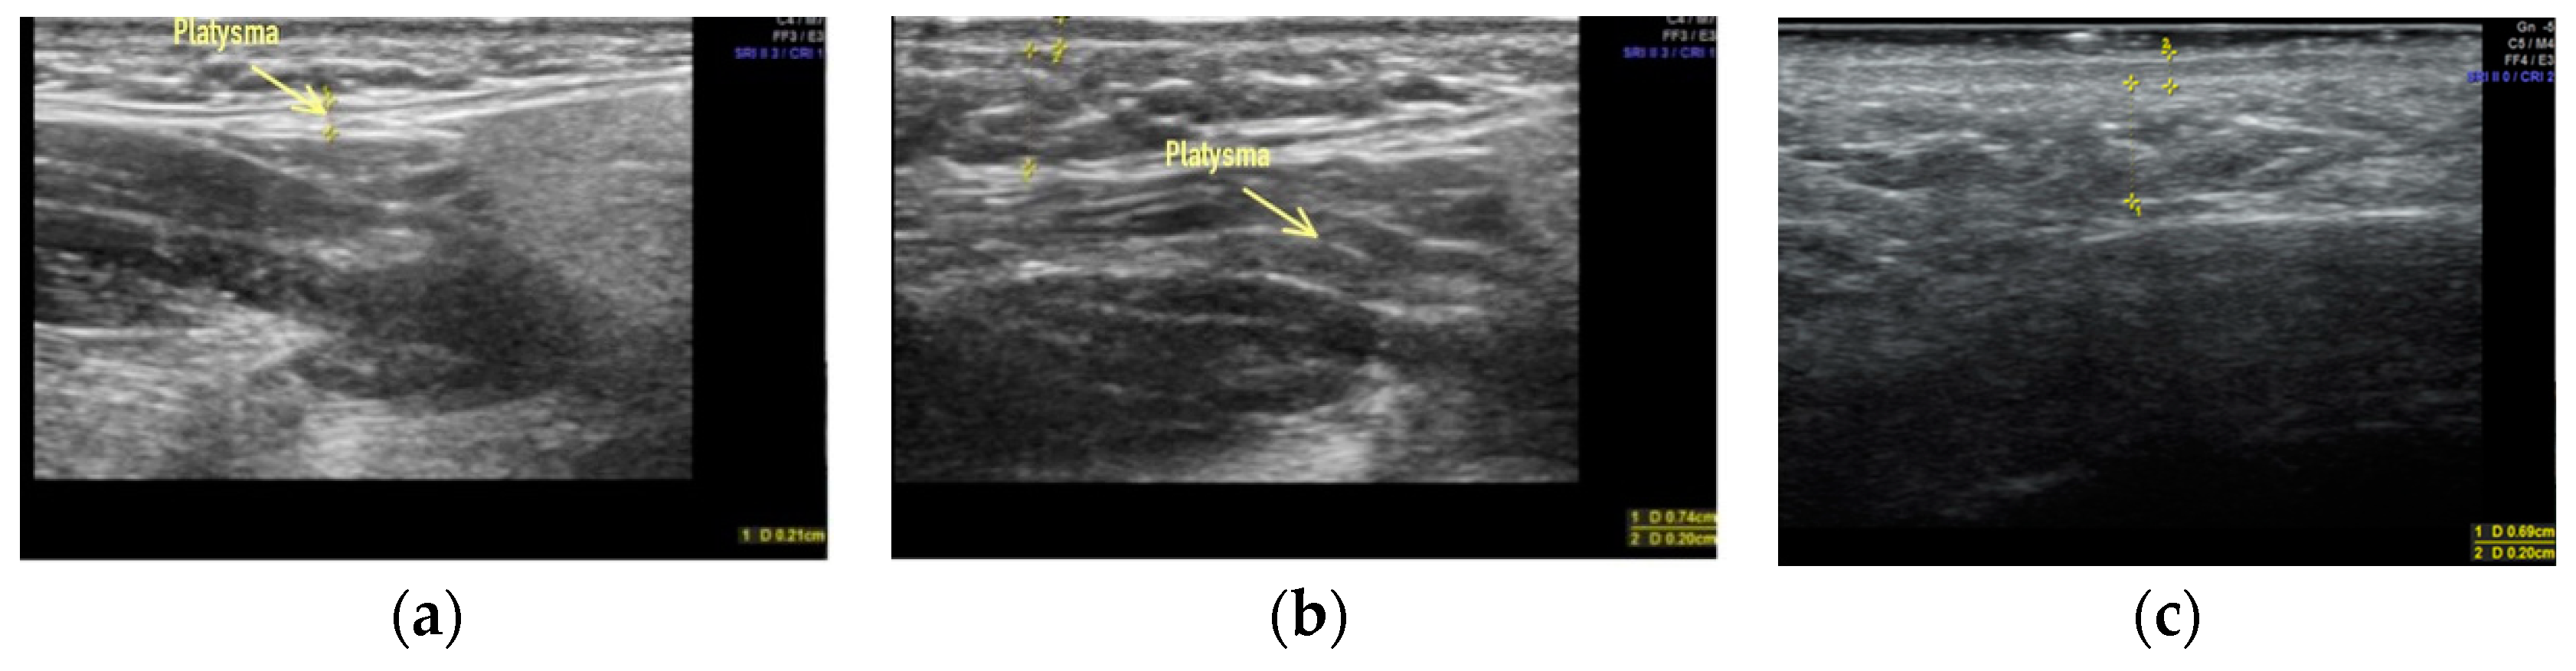

- Sharobaro, V.; Alimova, S.; Telnova, A.; Shamanaeva, L. Ultrasound diagnosis of age-related involutional changes in the lower third of face and neck to determine treatment techniques. Pak. J. Med. Sci. 2021, 37, 272–276. [Google Scholar] [CrossRef]

- Alimova, S.M.; Sharobaro, V.I.; Telnova, A.V.; Stepanyan, E.E. Planning of methods of surgical correction of soft tissues of the face and neck. Med. Vis. 2021, 25, 47–52. [Google Scholar] [CrossRef]